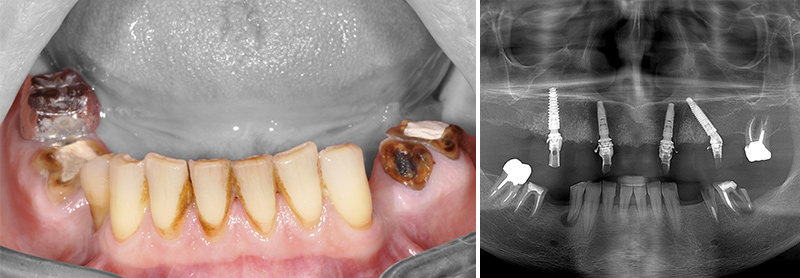

Fig. 36 et 37 : présentation du second cas.

Fig. 39 et 40 : les différentes vues du second cas.

Nous retrouvons maintenant comme précédemment les différentes vues du cas n°2 : l’os (en vert) et les dents segmentées (en rouge) et le rendu surfacique de l’arcade à l’état initial (en beige). À noter que bien que l’empreinte soit en couleur au format ply (fig. 38), les prothésistes convertissent le fichier en monochrome.